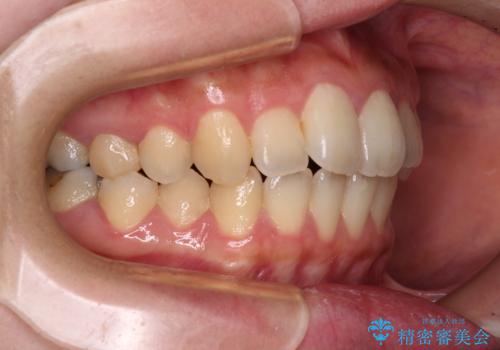

- 捻れた前歯が飛び出しており、口が閉じにくいとのことで来院された患者様です。

出っ歯というわけではないものの、前歯の捻転により口唇が押し出されている状態でした。

親知らずを抜去し、歯列全体を後方に移動させつつ、IPR(歯と歯の間を削る)でスペースを獲得し、インビザラインを用いて叢生を解消しながら前歯の突出を改善することとしました。